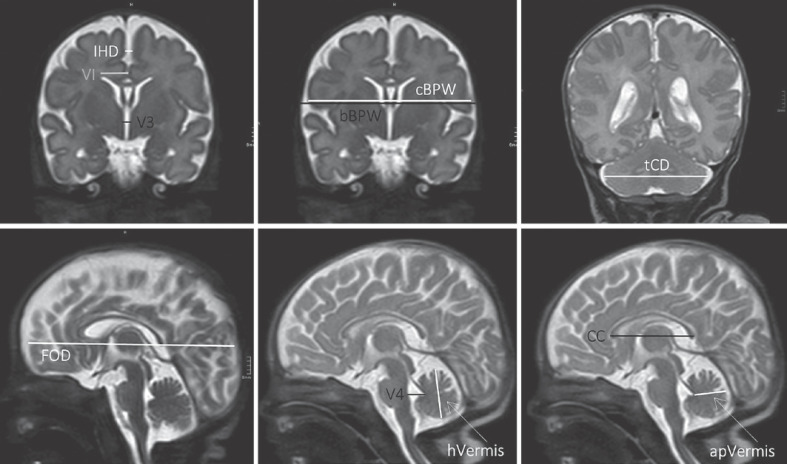

Introduction: Preterm birth and cerebral hemorrhage have adverse effects on brain development. Alterations in regional brain size on magnetic resonance imaging (MRI) can be assessed using 2D biometrical analysis, an easily applicable technique showing good correlation with 3D brain volumes.

Methods: This retrospective study included 74 preterm neonates with intraventricular hemorrhage (IVH) born <32+0 weeks of gestation between 2011 and 2019. Cerebral MRI was performed at term-equivalent age, and 2D measurement techniques were used for biometrical analysis and compared to normative data of two control groups. Finally, the correlation and association of brain parameters and patterns of impaired brain growth and outcome at 2 and 3 years of age were evaluated.

Results: Interhemispheric distance (IHD), the 3rd ventricle, and lateral ventricles presented larger, in contrast, cerebral biparietal width (cBPW), fronto-occipital diameter (FOD), and the length of the corpus callosum were smaller in IVH patients compared to respective controls. The strongest correlations with outcome were observed for the parameters FOD, anteroposterior diameter of the vermis, transverse cerebellar diameter (tCD), corpus callosum, 3rd ventricle, and left ventricular index. Patients with the small FOD, small BPW, and increased IHD pattern reached overall lower outcome scores at follow-up.